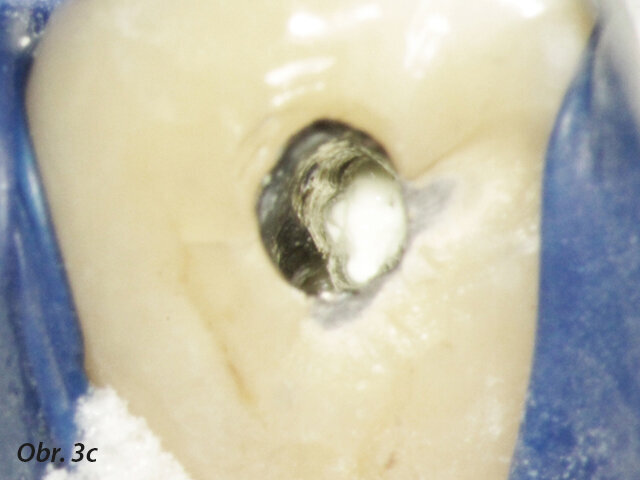

Perforace v dřeňové dutině nebo kořenovém kanálku významně mění prognózu zubu. Oprava perforace pomocí biokompatibilního těsnicího materiálu jako je MTA může ohrožené zuby ušetřit (Mente a spol. 2014) (obr. 3a–e).

Radiolucence v krčkové části špičáku

Aplikace PD MAP White pomocí MAP systému

Původní stav se zaplněnou perforací

Postoperační RTG se zaplněným kanálkem